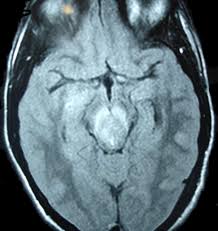

The basal ganglia are usually spared. Mri is the diagnostic modality of choice abnormal in 90%; Hsv encephalitis | radiology case | radiopaedia.org. Axial t2 prominent swelling, increase t2 signal involving the left temporal lobe and insular cortex. For a general discussion, and for links to other system specific manifestations, please refer to the article on hydatid disease. Herpes simplex (hsv) encephalitis is the most common cause of fatal sporadic fulminant necrotizing viral encephalitis and has characteristic imaging findings. Herpes simplex virus (hsv) is a human herpesvirus that causes hsv encephalitis (hse), which is the commonest fatal sporadic encephalitis in humans. Hse may result from primary infection or reactivation from latency, and it frequently involves frontal or temporal lobes, as well as the brain stem. The differential diagnoses include limbic encephalitis (paraneoplastic), gliomatosis cerebri, and status epilepticus. A brain biopsy was performed and the histology was consistent with encephalitis. For a general discussion, and for links to other system specific manifestations, please refer to the article on hydatid disease. Cerebral malaria is a rare intracranial complication of a malarial infection. Bilateral temporal lobe t2 hyperintensity refers to hyperintense signal involving the temporal lobes on t2 weighted and flair imaging.

For a general discussion, and for links to other system specific manifestations, please refer to the article on coccidioidomycosis. But changes are not specific for hsv (e.g. Multilocularis, and describes a spectrum of disease involving the spinal cord, the spine, or both. There is also some cortical ribboning seen on dwi. Cerebritis is a term that represents inflammation of the brain in the setting of infection, before the development of a cerebral abscess. Cerebral malaria is a rare intracranial complication of a malarial infection. Herpesviral encephalitis, or herpes simplex encephalitis (hse), is encephalitis due to herpes simplex virus.it is estimated to affect at least 1 in 500,000 individuals per year, and some studies suggest an incidence rate of 5.9 cases per 100,000 live births. Herpes simplex (hsv) encephalitis is the most common cause of fatal sporadic fulminant necrotising viral encephalitis and has characteristic imaging findings.

Herpes simplex (hsv) encephalitis is the most common cause of fatal sporadic fulminant necrotising viral encephalitis and has characteristic imaging findings.

The changes spare the basal ganglia, a feature which is helpful in distinguishing an mca infarct with hemorrhagic transformation from herpes simplex encephalitis, the diagnosis in this case. Hse may result from primary infection or reactivation from latency, and it frequently involves frontal or temporal lobes, as well as the brain stem. Herpes simplex (hsv) encephalitis is the most common cause of fatal sporadic fulminant necrotizing viral encephalitis and has characteristic imaging findings. It is usually bilateral but asymmetrical. The differential diagnoses include limbic encephalitis (paraneoplastic), gliomatosis cerebri, and status epilepticus. Two subtypes are recognized which differ in demographics, virus, and pattern of involvement. Given the history of fever and seizures coupled with the mri findings of bilateral mesial temporal lobe changes, herpes encephalitis requires clinical consideration. Spinal hydatid disease is an uncommon manifestation of hydatid disease, caused by the larval stage of echinococcus granulosus, or less commonly e. Multilocularis.the larval stage is the cause of hydatid disease in humans 1. The differential diagnoses include limbic encephalitis (paraneoplastic), gliomatosis cerebri, and status epilepticus. Herpes simplex encephalitis (hse) is the most common form of viral sporadic encephalitis and, when left untreated, has a mortality rate of 70% (3, 22). This patient went on to have hsv encephalitis proven on csf pcr. Bilateral temporal lobe t2 hyperintensity refers to hyperintense signal involving the temporal lobes on t2 weighted and flair imaging.